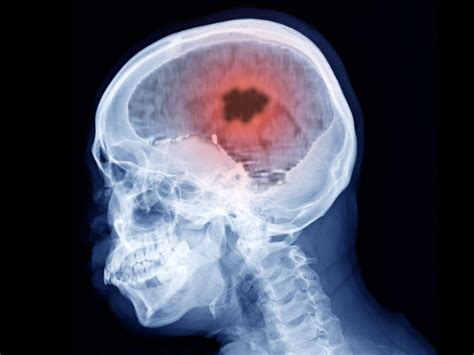

• Imaging tests: Magnetic resonance imaging (MRI) and magnetic resonance venography (MRV) are the most commonly used tests. These can provide detailed images of the brain and venous sinuses, helping to identify blood clots.

• Computed tomography (CT) scan: A CT scan can also be used to detect blood clots, especially in emergency situations.